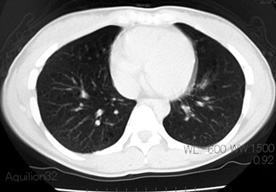

臨床的には進行性肺嚢胞化, くり返す肺気腫, 乳び性胸水貯留が特徴で, 多くの症例では進行性に呼吸不全となる*1

LAM患者さんに認められた両側肺気腫(右図:胸部CT)

初診時CT(左)から2年後のCTでは肺の嚢胞化が著明となっている。